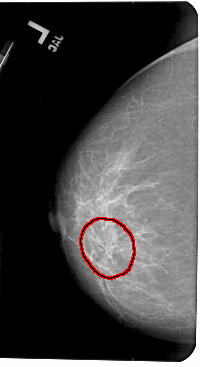

A_1436_1.LEFT_MLO

FILE: A_1436_1.LEFT_MLO.OVERLAY

TOTAL_ABNORMALITIES 1

ABNORMALITY 1

LESION_TYPE MASS SHAPE ARCHITECTURAL_DISTORTION MARGINS ILL_DEFINED

ASSESSMENT 4

SUBTLETY 3

PATHOLOGY BENIGN

TOTAL_OUTLINES 1

BOUNDARY